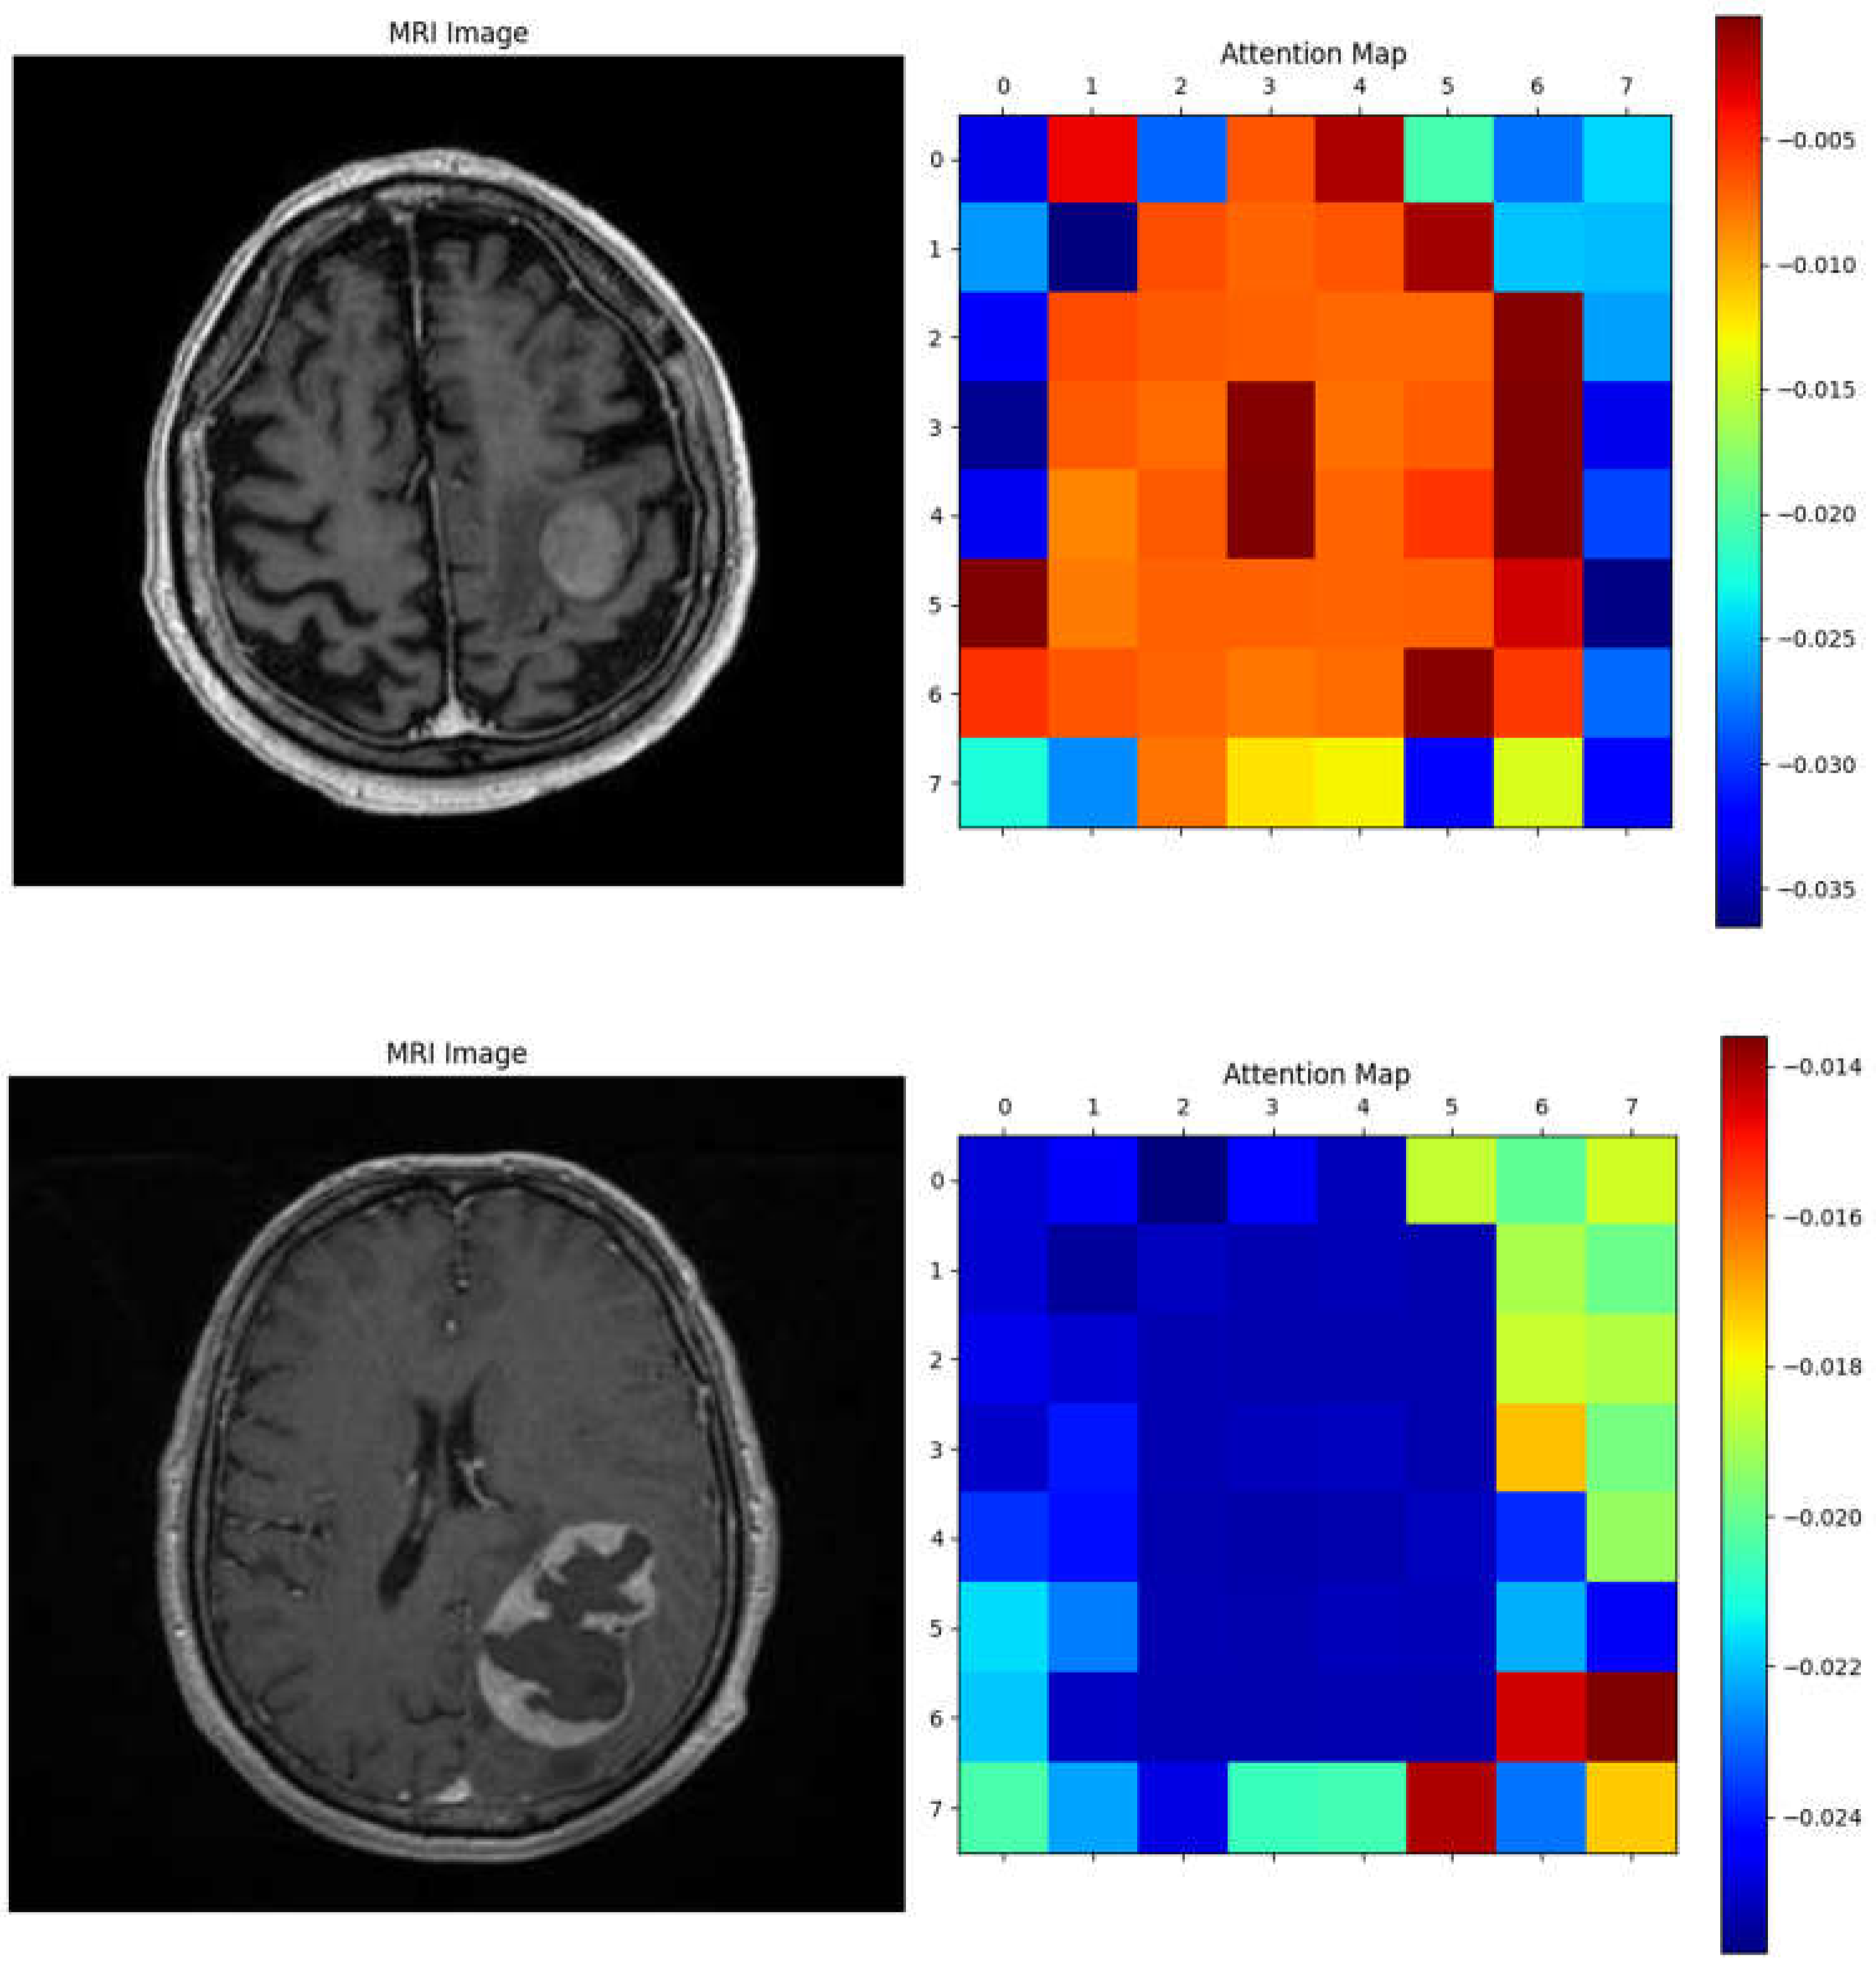

Figure 8 displays ten randomly selected MRI cases from the patient image database, showcasing the model’s performance in distinguishing between progression and regression patterns. Each image includes the ground truth label, the model’s prediction, and the predicted probability. Across these cases, the model accurately identifies both regression and progression with high confidence (probabilities close to or equal to 1.00).

These examples emphasize the model’s robust capability to differentiate between treatment response types, reinforcing its clinical relevance. Consistently high confidence levels indicate that the Vision Transformer model effectively recognizes patterns associated with each response type, thereby supporting its potential utility in real-world clinical settings for monitoring brain metastasis.

Figure 8. Specific patients cases (randomly chosen from the database) that demonstrates the model’s performance.